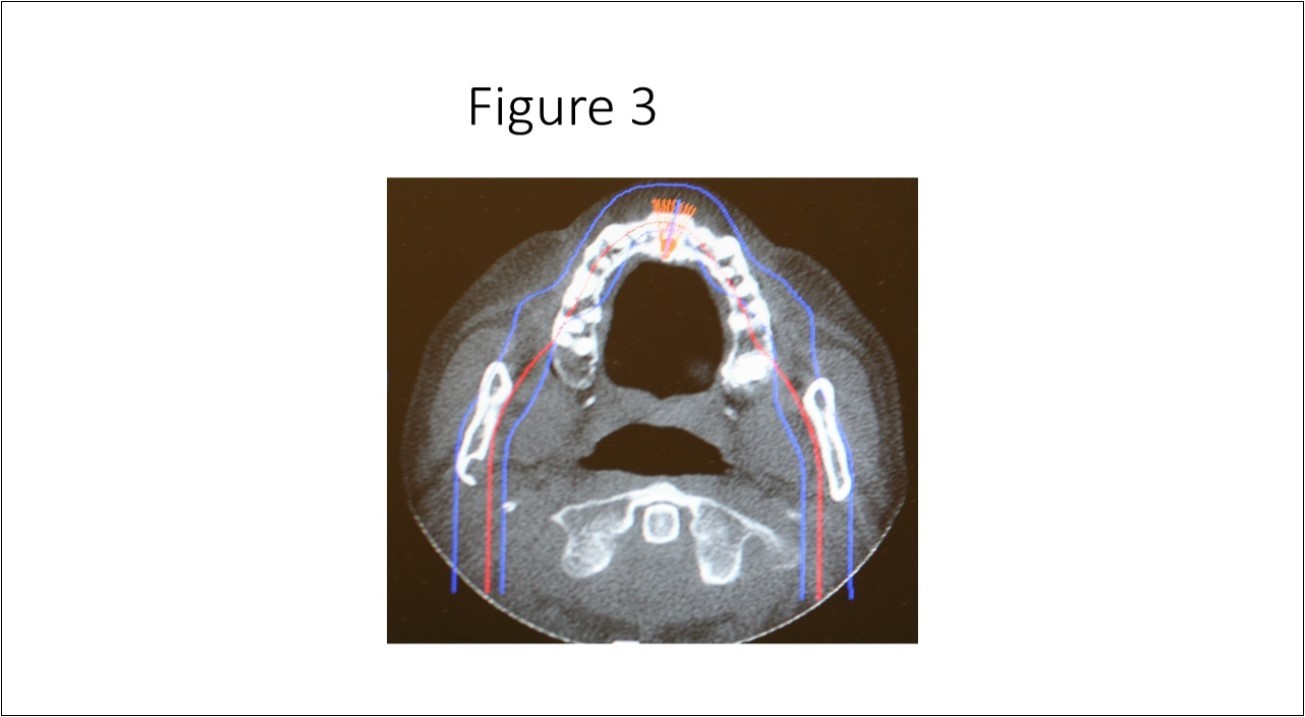

Maxillofacial examination was unremarkable. No facial swelling, masses or asymmetry was observed. The TMJ examination was normal. No pain or tenderness to digital palpation was observed in the right preauricular region. Oral examination of the patient was unremarkable. No trismus was observed as the maximal interincisive opening was greater than 40.0mm. No anterior or posterior open bite was observed. Imagining studies to rule-out intraosseous neoplastic lesions and arrive at a definitive diagnosis consisted of a panoramic radiograph and cone beam CT scan (120 kVp, 5 mA, 7.4 sec). Panoramic radiograph revealed a unilocular, well-circumscribed radiolucency in the right subcondyalar region of the mandible that was close to the posterior border of the condylar neck (Figure 2). Cone beam CT scan (i-CAT FLX, Imaging Sciences, Hatfield, PA) imaging revealed a well-defined unilocular, elliptical shaped radiolucent lesion on the medial surface of the right subcondylar neck of the mandible (Figure 3, Figure 4, Figure 5). The elliptical shaped unilocular lesion involved almost the entire horizontal dimension of the subcondylar neck (Figure 4). Figure 5 shows the three-dimensional CT scan reconstruction (i-CAT FLX, Imaging Sciences, Hatfield, PA) of the medial defect in the subcondylar region of the mandible. Based on knowledge of clinical head and neck anatomy and imaging studies, no treatment was indicated as the diagnosis was consistent with a variant of a Stafne bone cavity of the right subcondylar neck near the parotid gland and not a pathological condition. The patient was informed about the risk of condylar neck fracture due to the critical size of the SBC.

Figure 3.Axial cone beam CT scan showing osseous bone defect with herniation of soft tissue in the medial cortex of the right subcondylar neck of the mandible.

Stafne bone cavity located in the subcondylar region of the mandible is considered a rare variant of the well-described SBC in the mandibular posterior mandible first reported by Stafne in 1942. There is a paucity of published case reports of SBC identified in the subcondylar or ascending ramus of the mandible in the English world medical and dental literature.9,19In a study by Sisman et al 3using computed tomography they concluded that the SBC is due to the presence of aberrant submandibular gland tissue within the osseous defect on the medial surface of the mandible. As it is hypothesized that the submandibular gland tissue is entrapped that leads to an osseous concavity on the medial surface of the mandible, it is also plausible that the parenchymal tissues of the parotid gland can also become entrapped in the developing mandible that leads to a similar osseous concavity (Figure 3) in the subcondylar region of the mandible.20